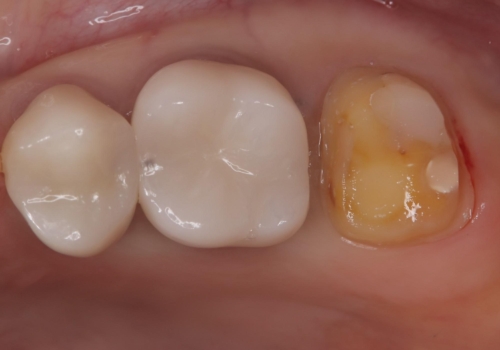

メタルインレーを除去したところ、残存歯質量が少なく破折のリスクを説明し、ゴールドクラウンでのやり替えとなりました。

保険のメタルインレーから二次う蝕予防(保険のメタルインレーは腐食しやすかったり、適合があまり良くなかったりで二次的にう蝕がインレー下で広がってしまうことが多々あります。)のためのやり替えだったため、材料としてセラミックとゴールドを提案したところ、展延性に優れ違和感の少ないゴールドを選択されました。